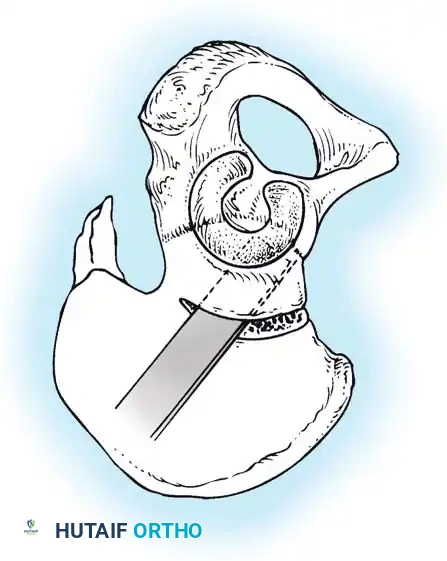

Anterior Approach (Smith-Petersen):

1. Incision: "Bikini" incision below the iliac crest.

2. Interval: Develop the plane between the tensor fasciae latae (superior gluteal nerve) and the sartorius (femoral nerve).

3. Deep Dissection: Detach the rectus femoris from the AIIS. Isolate and release the iliopsoas tendon at the pelvic brim to relieve the hourglass constriction of the capsule.

4. Capsulotomy: A T-shaped or I-shaped capsulotomy is performed parallel to the acetabular margin.

5. Joint Clearance: Excise the ligamentum teres, clear the pulvinar, and incise the transverse acetabular ligament inferiorly. Never excise the limbus, as it is critical for future acetabular growth; radial incisions may be made if it is severely inverted.

6. Capsulorrhaphy: Following concentric reduction, the redundant capsule is advanced superiorly and laterally to stabilize the joint.

Intraoperative view of the anterior approach to the hip, demonstrating capsulotomy and exposure of the dysplastic joint.